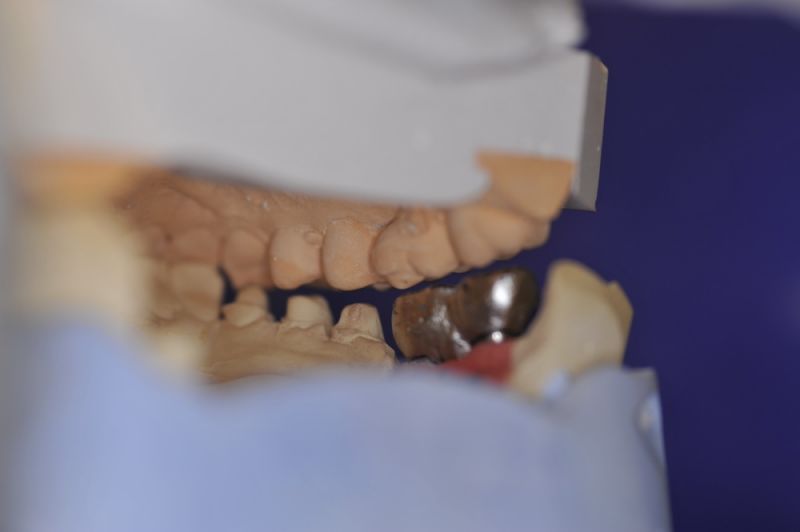

Mit dem heutigen Tag geht eine der technisch schwierigsten und anspruchsvollsten Arbeiten zu Ende, die im CMD-CENTRUM-KIEL jemals erstellt worden ist. Dabei sind es nur 10 Kronen, die benötigt werden, um die starken Kopf- und Gesichtsschmerzen der Patienten zu beseitigen.

1. Notwendigkeit einer implantatgestützten Kronenversorgung mit der Vorgeschichte, dass die Patientin eine Vielzahl von Behandlern aufgesucht hatte, die eine Implantation im Unterkiefer als nicht durchführbar einschätzten.

2. Extrem schlechte knöcherne Verhältnisse im Unterkieferseitenzahnbereich, die sich intraoperativ noch einmal als ungünstiger darstellten, als bereits in den Voruntersuchungen erkennbar.

3. Sehr dünne Implantate, die von ursprünglich zwei je Kieferhälfte auf letztendlich drei je Kieferhälfte umgeplant werden mussten.